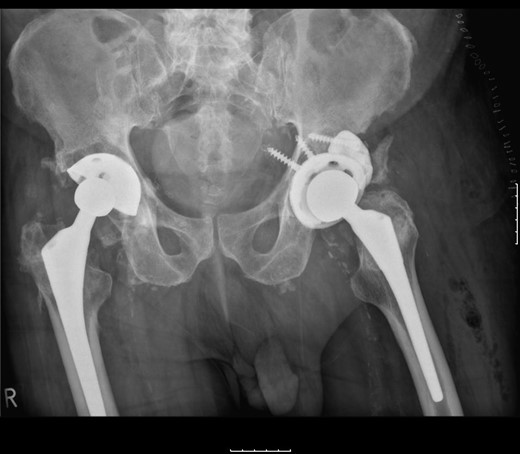

Pelvic radiographs demonstrated that the femoral head had migrated superolaterally through the polyethylene (PE) liner and the acetabular cup with metallic fragments inferior to this, and was articulating with the superior wall of the acetabulum causing bony destruction. There was no radiographic evidence of loosening to the stem (Fig. 1).

Pelvic radiograph demonstrating superolateral migration of the femoral head, metallic fragments around the neck and bony destruction of the acetabular wall.